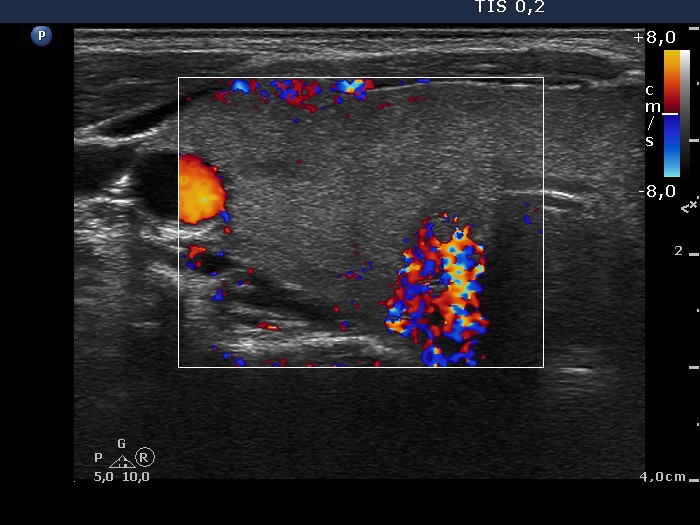

Graves' disease - Case 1049

Follow-up investigation 40 months after first visit (ultrasonographic picture 3)

Patient on daily 5 mg methimazole therapy in hypothyroid state

Right lobe, transverse scan, color Doppler mode. The vascularization is minimal.